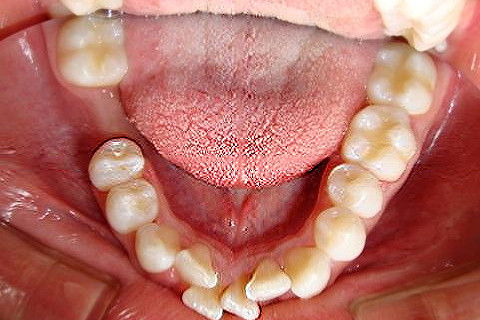

Paciente D. F. S., 19 anos, com queixa principal o apinhamento superior e inferior. Realizado o diagnóstico foi proposto duas opções de tratamento: exodontia de 04 pré-molares ou exodontia de incisivo inferior e slices superior, verticalização do molar 47 para futura instalação de implante do 46.

O tratameno foi iniciado com a montagem completa do aparelho superior e inferior, a indicação da exodontia do elemento 41, alinhamento e nivelamento.

Atualmente estamos com  04 meses de tratamento, podemos notar uma grande evolução no caso em pouco tempo.